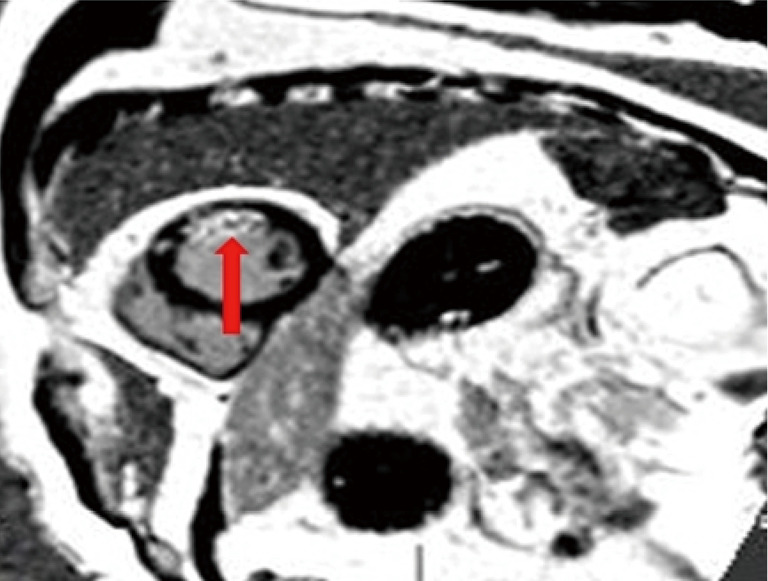

Background: In the context of acute ST-segment elevation myocardial infarction (STEMI), epicardial fat volume (EFV) has a significant impact on the formation of microvascular obstruction (MVO). This study aimed to quantitatively measure the EFV and myocardial strain parameters by cardiac magnetic resonance (CMR) and to explore their relationship with the presence or absence of mcrocirculation dysfunction after myocardial infarction.

Methods: This was a retrospective study. From June 2022 to December 2023, 56 consecutive patients diagnosed with acute STEMI who underwent percutaneous coronary intervention (PCI) were selected from The First Affiliated Hospital of Bengbu Medical University. Patients were divided into two groups based on the presence of MVO group and the non-MVO (NMVO) group, with 22 cases (39%) and 34 cases (61%) respectively. The characteristics of the infarction were assessed by delayed enhancement with gadolinium. Based on standard cine images, the global circumferential strain (GCS), global radial strain (GRS), and global longitudinal strain (GLS) of the left and right ventricles were evaluated using CMR feature tracking (CMR-FT) imaging. The volume of EFV was quantified along the short-axis slices of the left and right ventricles at the end of diastole by CMR imaging. The differences in baseline characteristics, EFV, and myocardial strain parameters between the groups were compared using Pearson or Spearman correlation analysis. The specificity and sensitivity of myocardial strain parameters in predicting MVO were obtained using receiver operating characteristic (ROC) curves. The predictive factors for MVO were analyzed using univariate and multivariate logistic regression analyses.